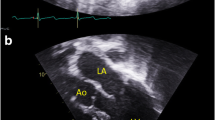

Individual 1 (F1:IV-2) is a 19-year-old man hemizygous for a novel NAA10 c.16G>C p.(A6P) variant (Fig. 1A; Table 1). He has ID and hypertrophic cardiomyopathy with a family history suggesting an X-linked cause. The proband had a sister (F1:IV-1) who was born with an interrupted aortic arch and died at 10 days of life. Both of his living sisters and parents are healthy and had normal regular echocardiograms. A maternal uncle (F1:III-5) had ID, medullary sponge kidneys with renal failure, and died at age 40 from complications of an idiopathic restrictive cardiomyopathy. No one else in the family has been found to have medullary sponge kidneys or recurrent kidney stones, so this is not likely to be caused by NAA10 impairment. There were concerns about the proband’s development from about 15 months of age. His mother reported that he was saying “mama” and “dada” at that age but stopped and did not start using words again until almost age 4 years. There were no concerns about his early motor development. He had issues with attention, concentration, and could be oppositional with his parents, teachers, and providers. He received special education all through school. Formal neuropsychological testing was attempted a number of times but without completion due to a lack of cooperation and effort. The neuropsychologist provided an estimated IQ < 60 based on what he was able to complete. At the completion of high school, he was reading at a 2nd-grade level and doing math at a 3rd-grade level.

Hypertrophic cardiomyopathy was diagnosed at age 7 years. Regular follow-up since that time has confirmed persistent and stable asymmetric septal hypertrophy, most recently with a thickness of 18 mm without obstruction. He had no issues with fatigue, shortness of breath, chest pain, syncope, nor near syncope.

Individual 6 is a 17-year-old female who was found to be heterozygous for the previously studied pathogenic NAA10 c.384T>G p.(F128L) variant (Saunier et al. 2016; Cheng et al. 2019) (Fig. 1C; Table 1). She was born at 34 weeks of gestation, with birth weight 2500 g (75th percentile). She was number one of fraternal twins. Her twin is healthy, with no health issues. In addition, she has two other healthy brothers. Early issues included respiratory distress, requiring supplemental oxygen for about 6 weeks. She was subsequently noted to have global DD and multiple contractures, including elbows and feet. There have been some issues with poor weight gain. She has central vision impairment, microcephaly and occasional tremors. She can walk with assistance but is frequently in a wheelchair. She was still incontinent at age 15 years. She was followed by paediatric cardiologists, and ECG and echocardiogram were unremarkable. At age 15 years, weight was 29.4 kg (< 3rd percentile, − 3 SD), height was 133.6 cm (< 3rd percentile, − 3 SD), and head circumference 48.2 cm (< 3rd percentile, − 3 SD). Findings at that time included contractures at the major joints, spasticity, and dysconjugate gaze. Laboratory evaluation included testing for Prader–Willi (OMIM #176270) and Angelman (OMIM #105830) syndromes, karyotyping, serum acylcarnitine profile and array CGH (comparative genome hybridisation), all of which were normal. The de novo NAA10 variant was identified using clinical exome sequencing.

Clinical report: family 4, individual 7

Individual 7 (F4:II-1) is a 33-month-old girl with a novel de novo NAA10 c.386A>C p.(Q129P) variant (Fig. 1D; Table 1). She was born at 41 weeks of gestation with birth weight of 2910 g (23rd percentile) and birth length of 47 cm (12th percentile). She had perinatal distress requiring resuscitation. Apgar scores were 1, 3, and 9. Prenatal MRI showed hypoplastic cerebellar vermis and hypoplastic pons. Subsequent imaging after birth showed cerebellar vermian hypoplasia with cystic dilatation of the 4th ventricle. She also had a left pneumothorax. A heart murmur was noted, and she was found to have a small patent ductus arteriosus, enlarged atrial septal defect and Ebstein anomaly of the tricuspid valve. Bilateral vocal cord paralysis was noted. She had nutritional issues which required feeding with first gastrostomy tube and subsequently with a gastro-jejunostomy tube. Physical findings at 33 months included a bowed upper lip, thickened gingiva, upper lid ptosis, prominent globes, a short columella, microcephaly, bilateral Sydney lines, and a heart murmur. At age 33 months, she “babbles” but has no words. She can use a standing device but is not walking independently. A chromosomal microarray showed a 47, XXX karyotype, but as this finding could not explain her clinical picture, exome sequencing was carried out detecting the NAA10 variant on one of her X chromosomes.